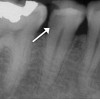

Obtaining a pretreatment pulpal and periradicular diagnosis before performing restorative treatment helps the clinician better understand how to treat the dental pulp, especially if it is exposed during caries excavation (Figure 1). A recent study by Ricucci et al found that a clinical pulpal diagnosis of a normal pulp or reversible pulpitis had a 96.6% histological match to the actual pulp tissue in a tooth.17 Therefore, for patients who present with or without pain from a carious pulp exposure and a pulp diagnosis of a normal pulp or reversible pulpitis, the tooth can be successfully treated with a mineral trioxide aggregate (MTA) pulp capping or pulpotomy if the pulp is exposed during treatment.18 In a randomized clinical trial, Hilton et al reported that MTA performed significantly better than calcium hydroxide as a direct pulp-capping agent.19

Fig 1. Obtaining a pretreatment pulpal and periradicular diagnosis prior to restorative treatment allows the clinician to properly treat the dental pulp if exposed during caries removal. Here, radiographic evidence of decay is shown on tooth No. 29 (arrow).